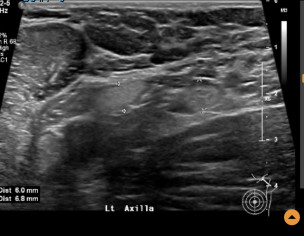

Left breast ultrasound report said no concerns. Symptoms - enlarged lymph nodes left breast, small cyst, changes in size and shape of left breast, dimples in lower left breast, pain in outer quadrant of left breast. Second opinion on ultrasound pics?